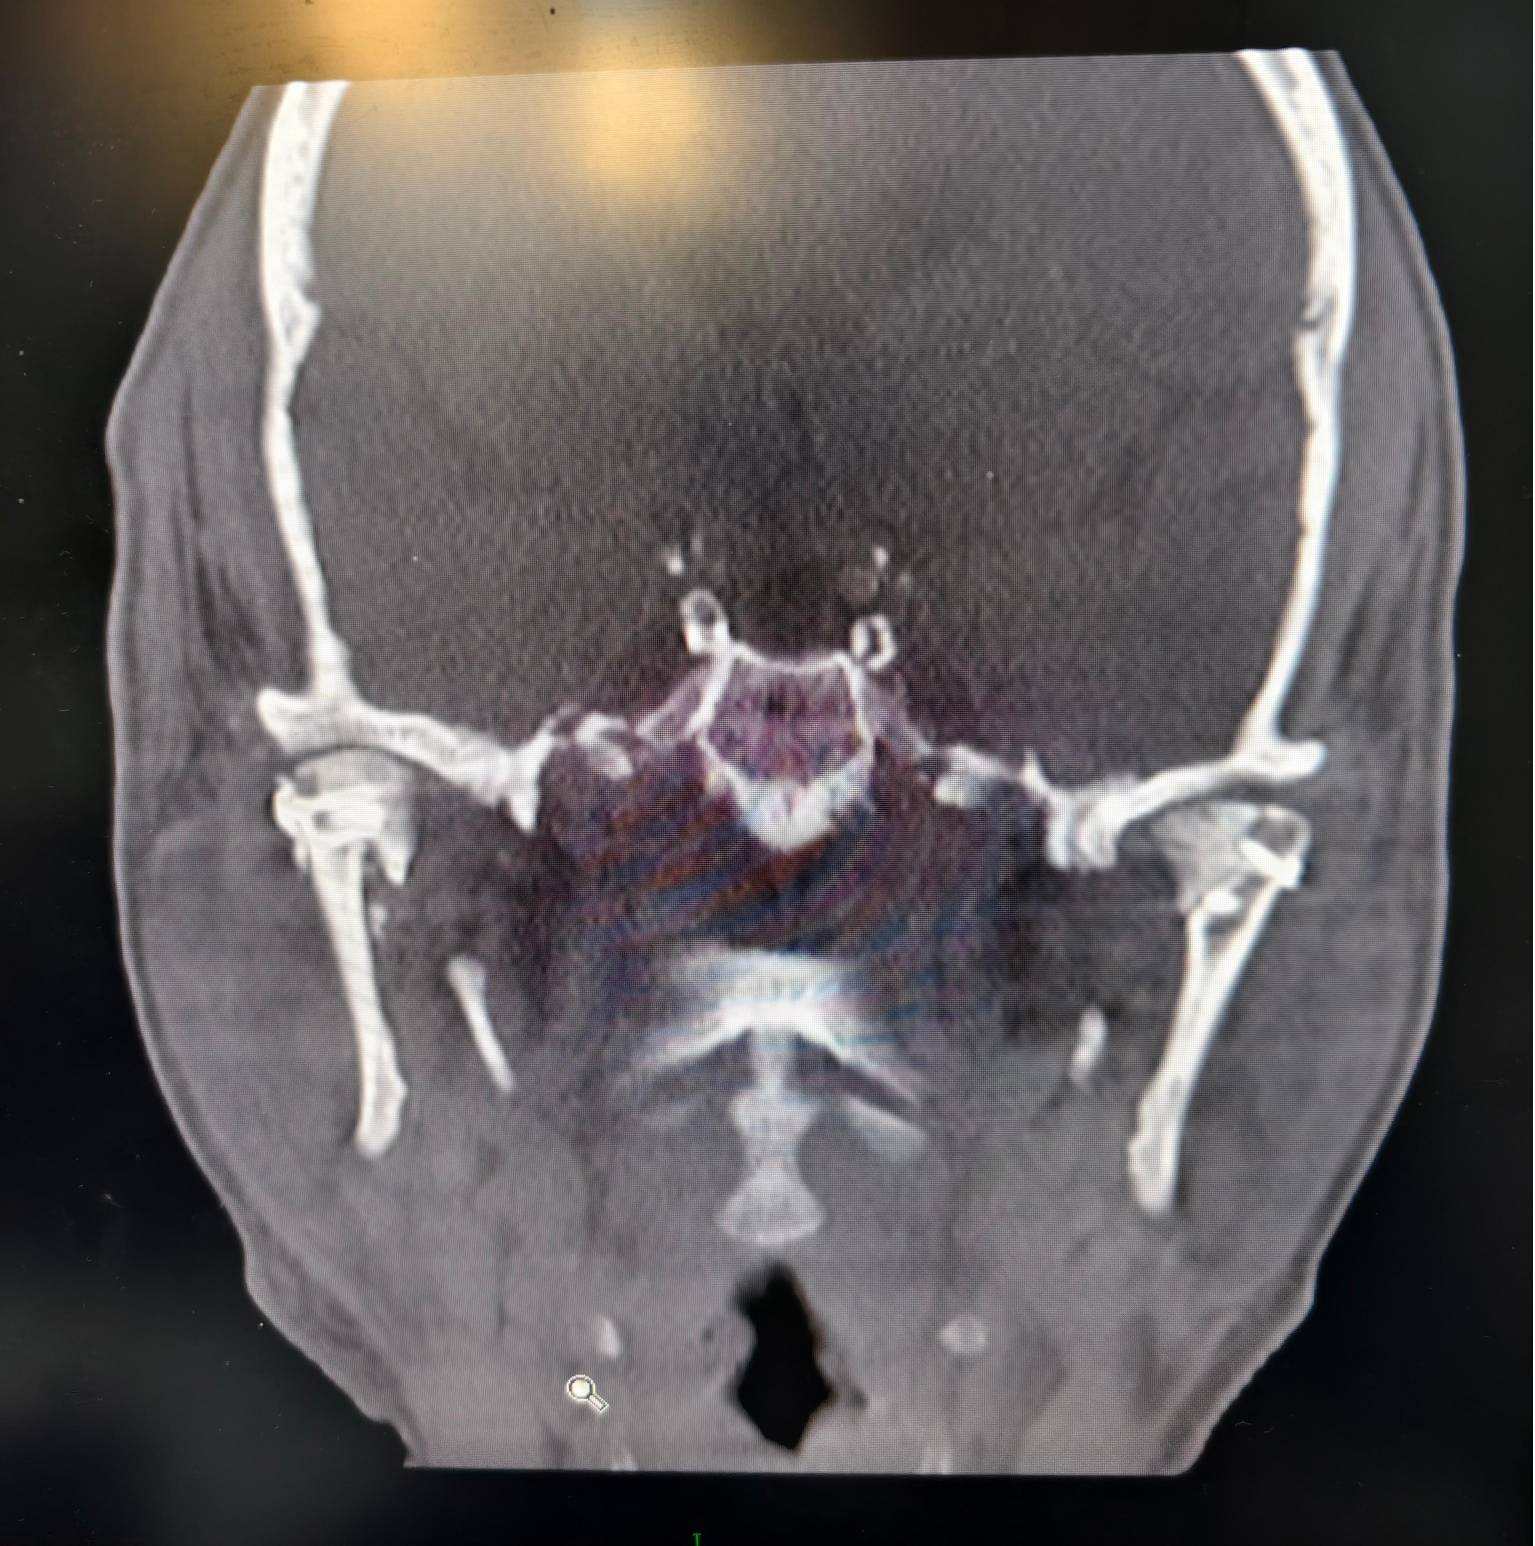

借助该模型,让团队能够在术前精准模拟手术过程,详细规划骨折复位路径和内固定方案、提前进行内固定物的预制,大大提高了手术的精准性与安全性。在充分准备后,团队在主任医师胡沛与副主任医师马莉共同带领下为姬先生成功实施了陈旧性双侧上颌骨骨折切开复位内固定术、陈旧性创伤性腭裂、陈旧性双侧髁状突骨折切开复位内固定术、陈旧性下颌骨骨折切开复位内固定术,同时还利用患者的骨折部位,纠正了患者受伤前的上颌前突、开??畸形。历经八小时,手术过程顺利,术后姬先生恢复状况良好。

术后